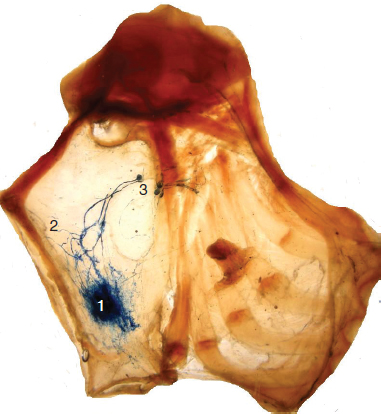

The system starts in the interstitial space with the initial lymphatic capillaries (Fig. 6-1). It drains the lymph through the collecting vessels, which is then filtered in the lymph nodes and finally cleared into the venous system. It is distributed throughout the body, except for the central nervous system, where the perivascular spaces have a prelymphatic or paralymphatic function.

FIG. 6-1 Imaging of 1, the lymph capillaries and 2, blood vessels.